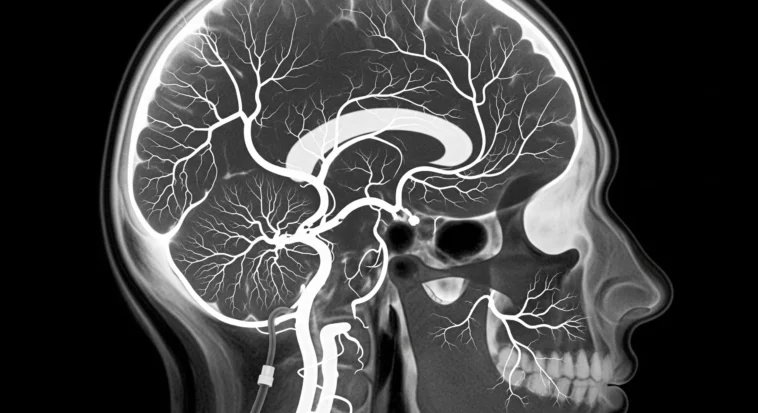

Doctors inject a special dye that lights up your arteries and veins on X-rays, showing blood flow in real time. It’s way more detailed than regular scans—like switching from blurry photos to HD video.

It’s more intense, but the images are insanely clear—like seeing every crack in the road. Doctors use this when details really matter.

- Exceptional Detail: Provides the most comprehensive visualization of brain blood vessels available

- Real-Time Imaging: Captures blood flow dynamics, not just static vessel structure